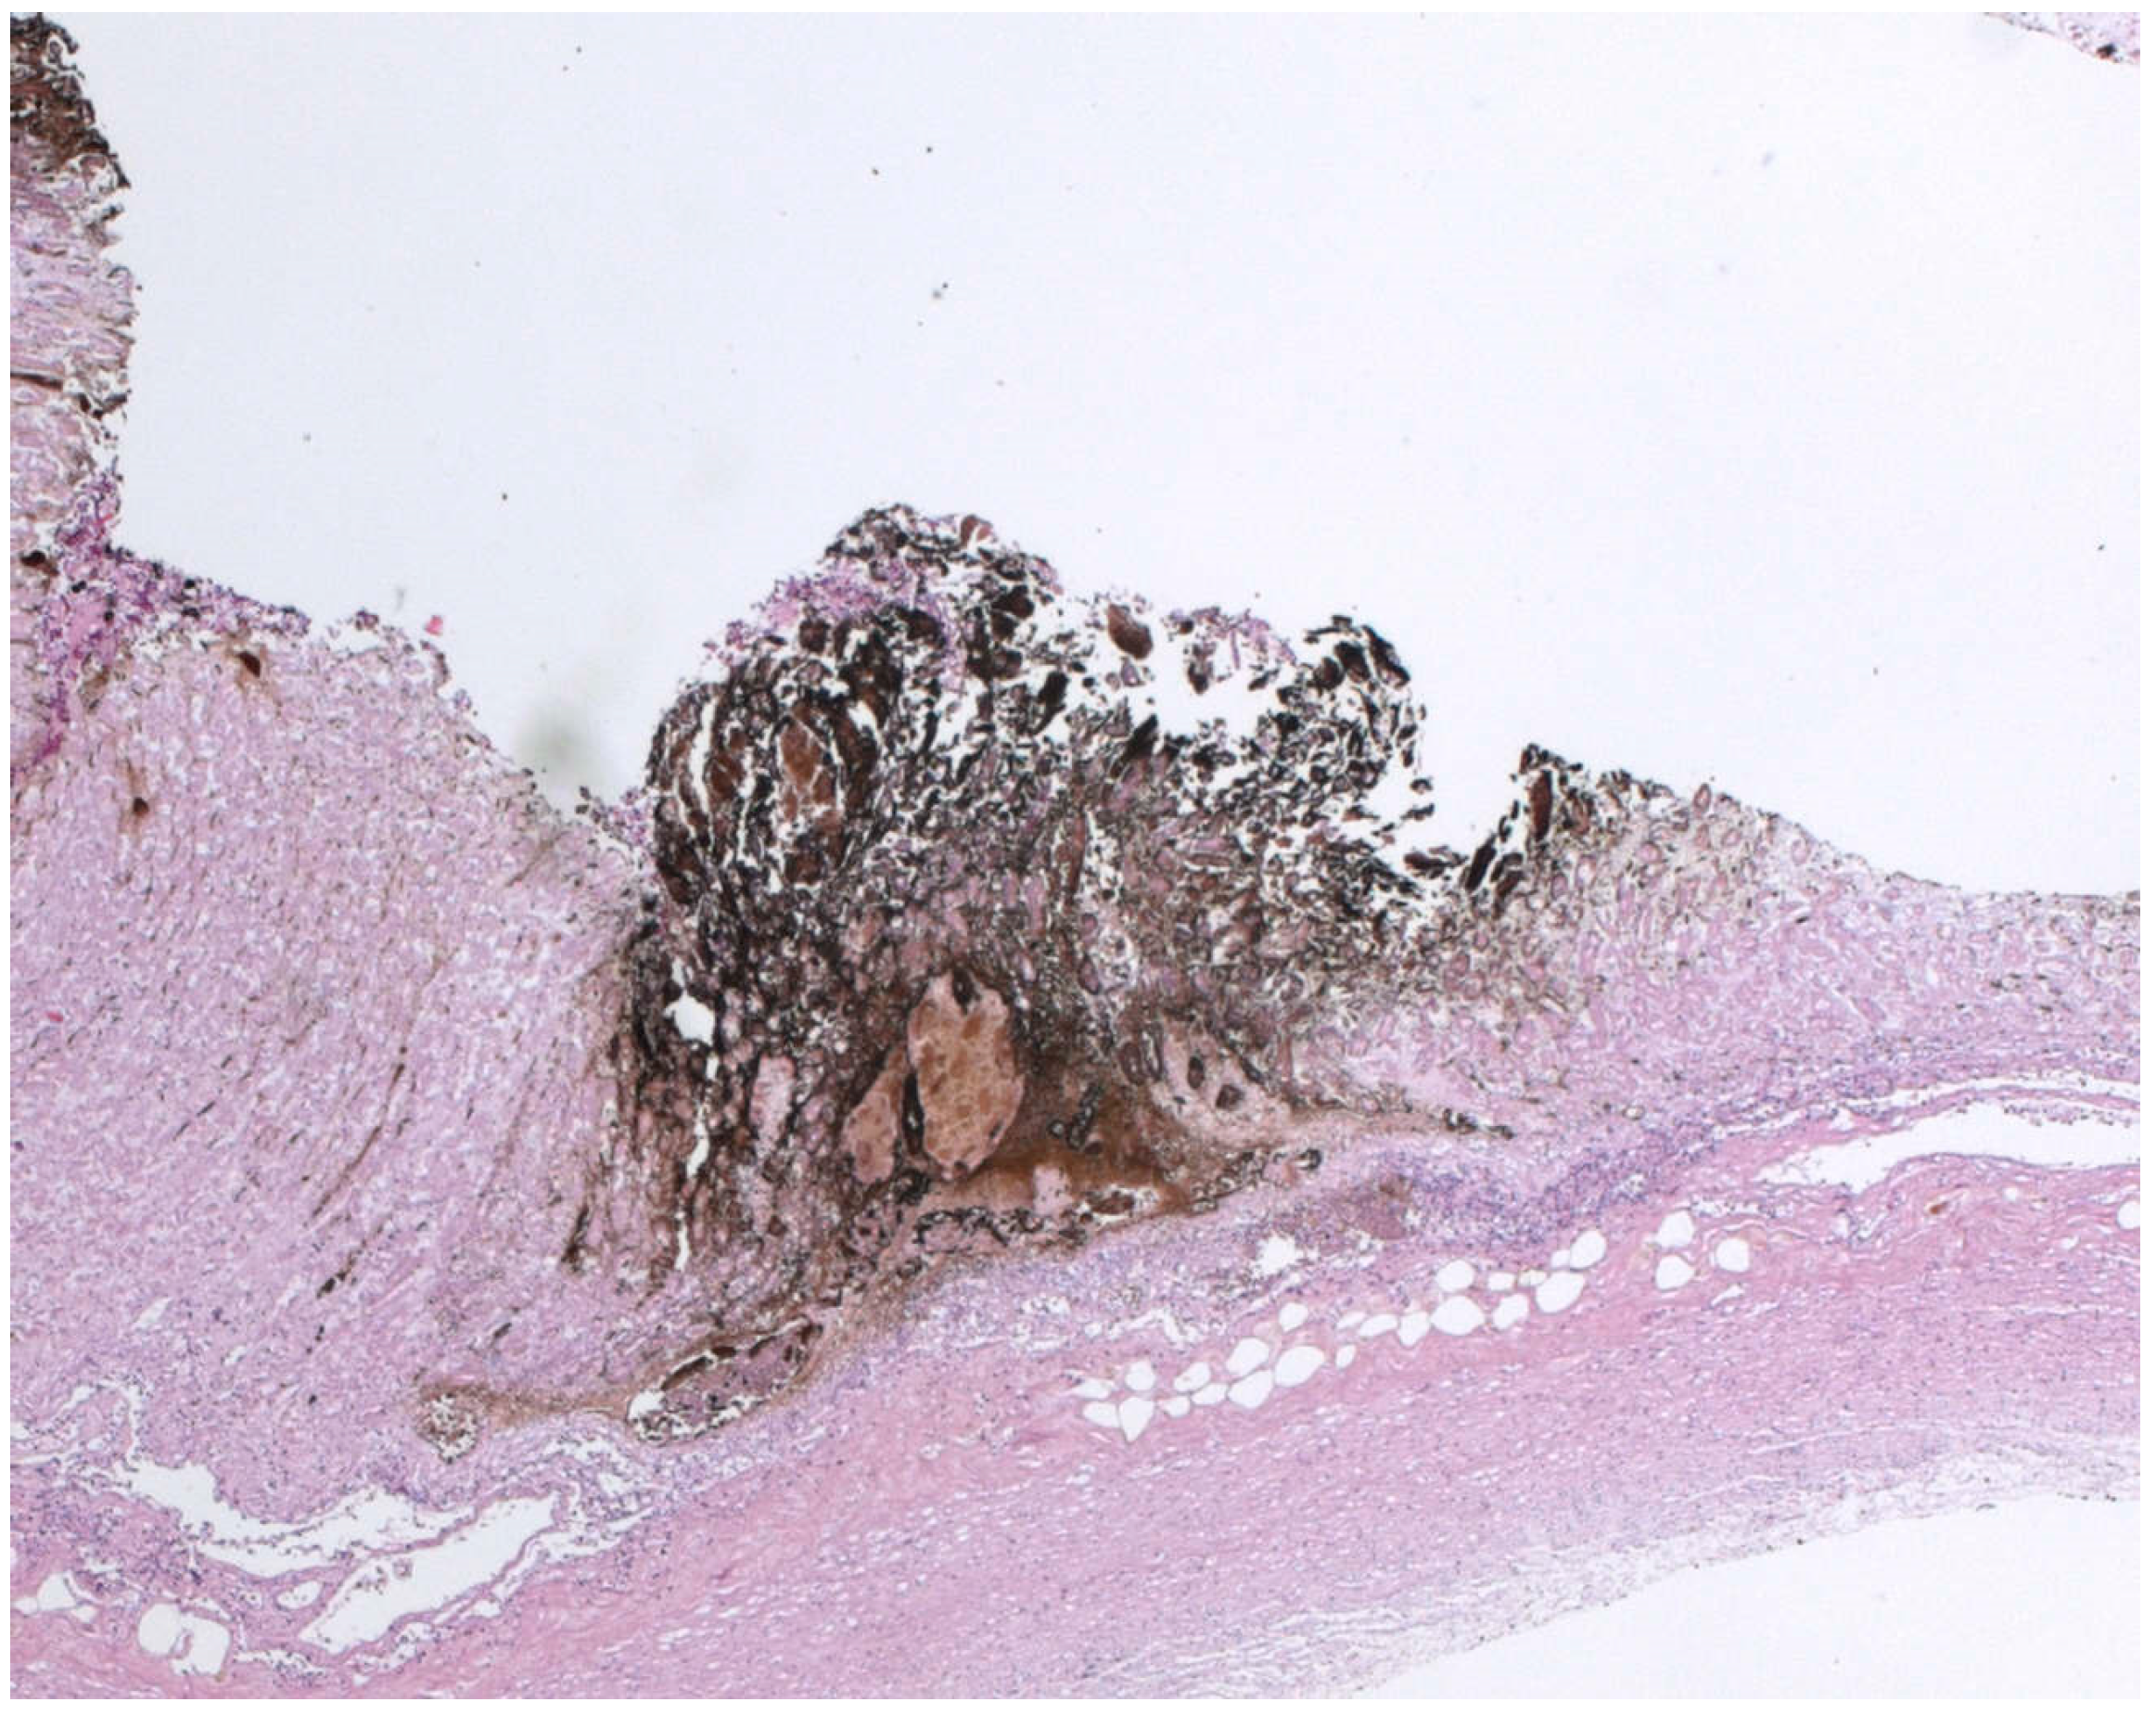

Biological Mechanisms behind Wischnewsky Spots Finding on Gastric Mucosa: Autopsy Cases and Literature Review

3.1.1. Case 1

3.3.1. Case 1